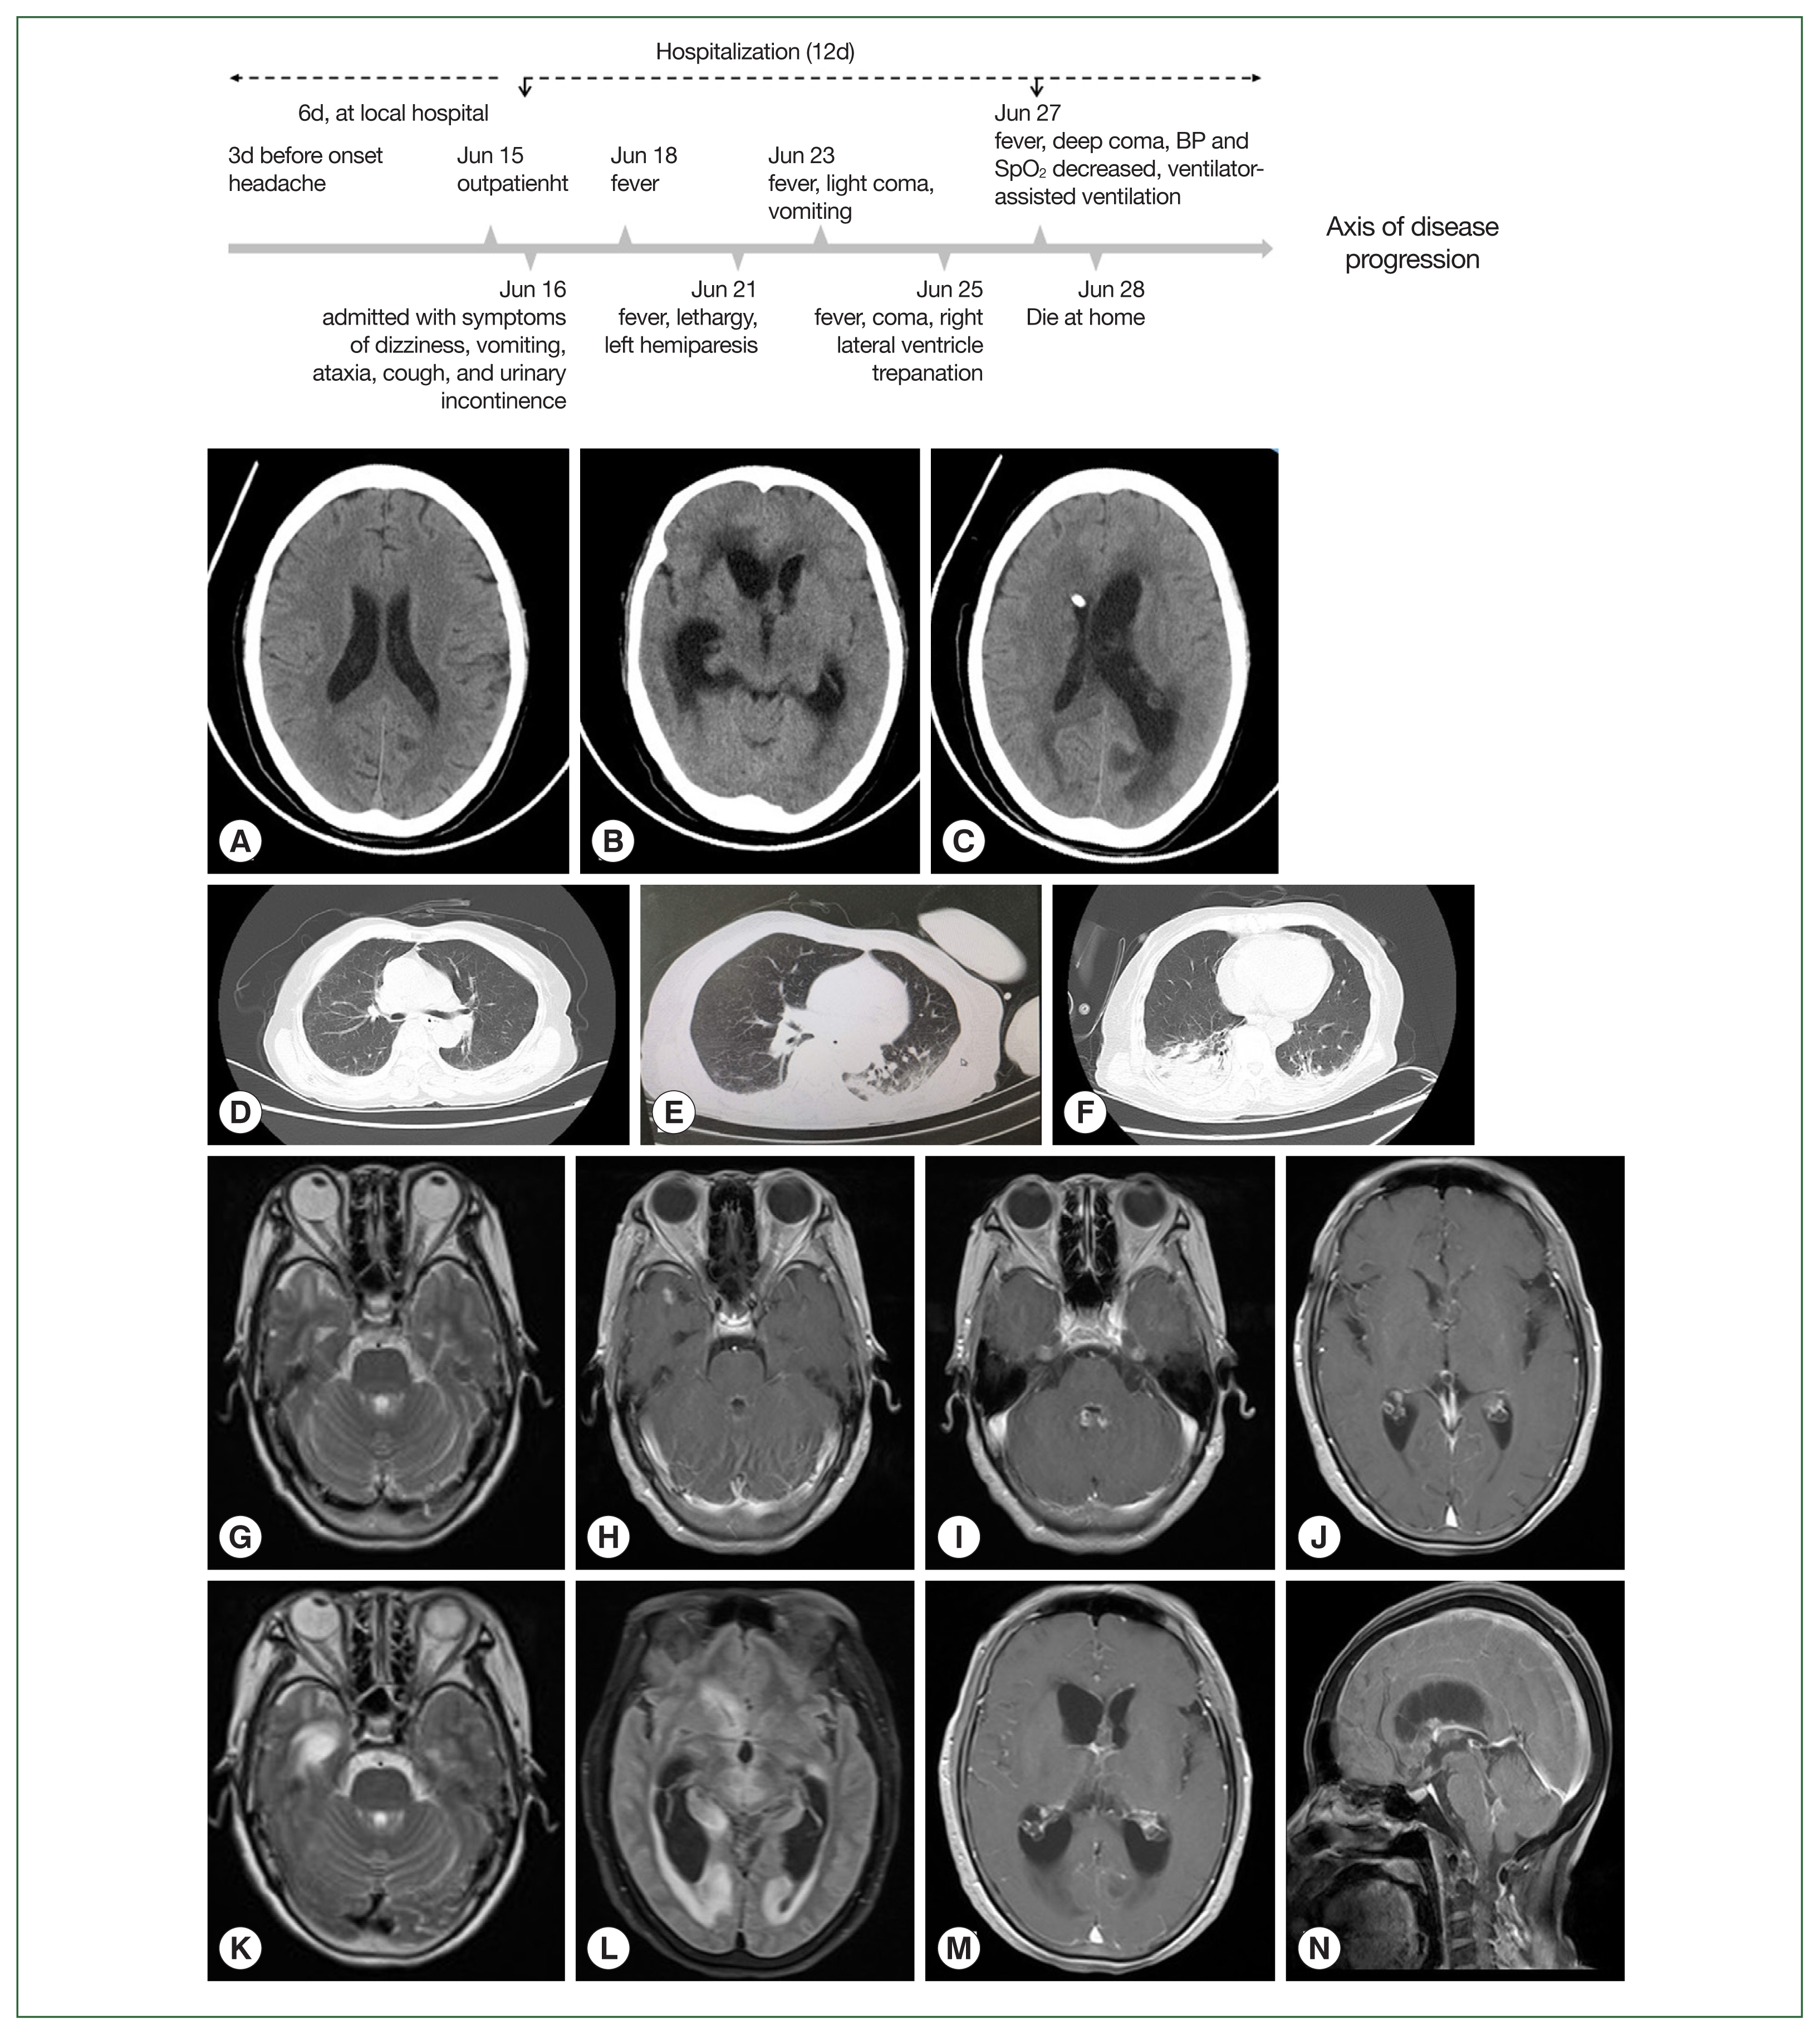

Diagnosing Balamuthia mandrillaris amebic meningoencephalitis in a 64-year-old woman from the Southwest of China

Suhua Yao, Xiaoting Chen, Lian Qian, Shizheng Sun, Chunjing Zhao, Zongkai Bai, Zhaofang Chen, Youcong Wu

Parasites Hosts Dis 2023;61(2):183-193.

Published online May 23, 2023

DOI: https://doi.org/10.3347/PHD.23039

Balamuthia mandrillaris amebic encephalitis (BAE) can cause a fatal condition if diagnosis is delayed or effective treatment is lacking. Patients with BAE have been previously reported in 12 provinces of China, with skin lesions being the primary symptom and encephalitis developing after several years. However, a significantly lower number of cases has been reported in Southwest China. Here we report an aggressive BAE case of a 64-year-old woman farmer with a history of skin lesions on her left hand. She was admitted to our hospital due to symptoms of dizziness, headache, cough, vomiting, and gait instability. She was initially diagnosed with syphilitic meningoencephalitis and received a variety of empirical treatment that failed to improve her symptoms. Finally, she was diagnosed with BAE combined with amebic pneumonia using next-generation sequencing (NGS), qRT-PCR, sequence analysis, and imaging studies. She died approximately 3 weeks after the onset. This case highlights that the rapid development of encephalitis can be a prominent clinical manifestation of Balamuthia mandrillaris infection.